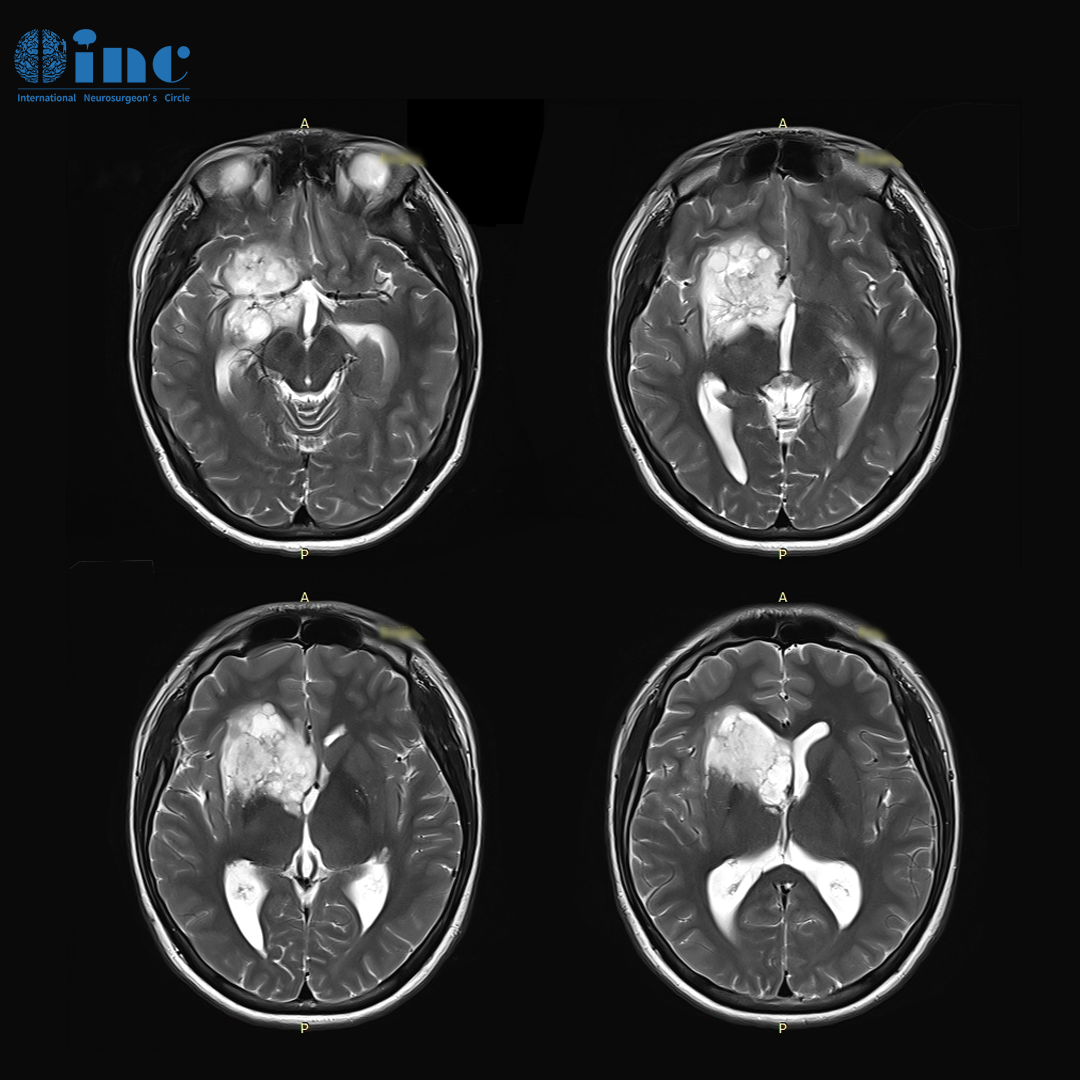

基底節(jié)膠質(zhì)瘤案例

基底節(jié)膠質(zhì)瘤案例圖

基底節(jié)膠質(zhì)瘤